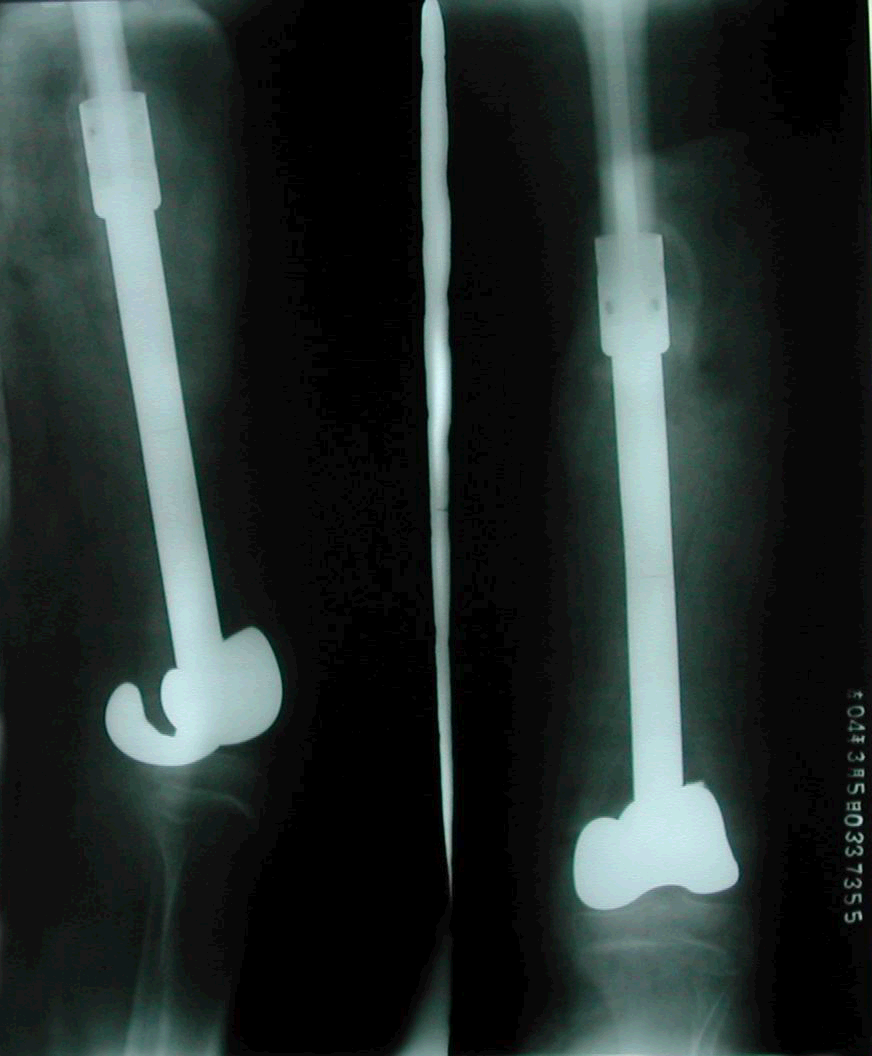

2、病例2:女 10岁 左股骨下端普通型骨肉瘤并病理性骨折,大剂量化疗后行肿瘤边缘切除定制型假体置换术,术后局部复发截肢,2年后肺转移死亡。

图 7术前X线片

a:正位 b:侧位

图 10 术后X线片

图 11 术后7个月局部复发

图 12 术后1年肺转移